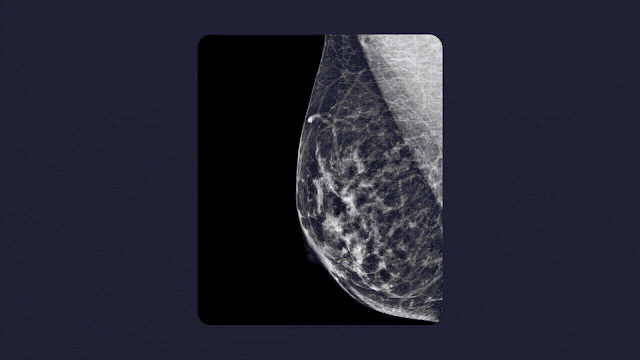

显然,加速发布与健康相关的 ML 技术是很有必要的。例如,在肿瘤学领域,乳腺癌和肺癌是两种最常见的癌症类型,对于二者而言,早期发现都是关键。如果 ML 能够提高这些癌症筛查的准确性,扩展其可用范围,患者将从中受益,但是等待部署这些进展的时间越长,得到帮助的人就会越少。建立伙伴关系可以让新技术更快而安全地触达患者——成熟的医疗技术公司可以将新的 AI 能力整合到现有的产品组合中,寻求适当的监管许可,并利用他们现有的客户群快速部署这些技术。

谷歌研究回顾2022年健康领域进展:达成多个合作,迈向移动医疗

我们已经亲眼见证过类似成就的达成。Google 发表了利用 ML 改善乳腺癌筛查的领先研究成果,仅仅两年半之后,我们就与一家领先的乳房 X 线摄影软件供应商 iCAD 合作,开始将我们的技术整合到 iCAD 的产品中。通过与 RadNet 的子公司 Aidence 合作,我们发现,在将低剂量 CT 扫描的深度学习研究转化为肺癌筛查工作流程时,也实现了同样的进展加速。